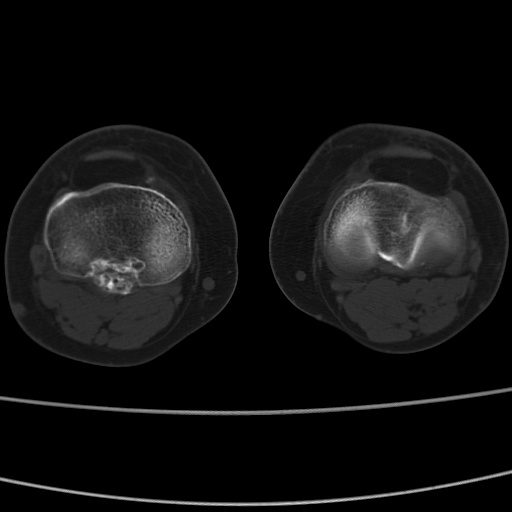

女性,50岁。【请提供患者临床症状体征】

右膝关节退行性改变,关节游离鼠。

右膝关节退行性改变,滑膜黏液囊钙/骨化并游离。